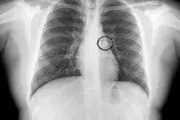

• ریه‌های این دختر عجیب دندان دارد!+ عکس

ریه‌های این دختر عجیب دندان دارد!+ عکس

پدر و مادر نگران با عجله دختر 9 ساله شان را به بیمارستان بردند تا متوجه واقعیت ماجرا شوند ؛ نتیجه ی عکسبرداری اورژانسی آنها را حیرت زده ساخت.